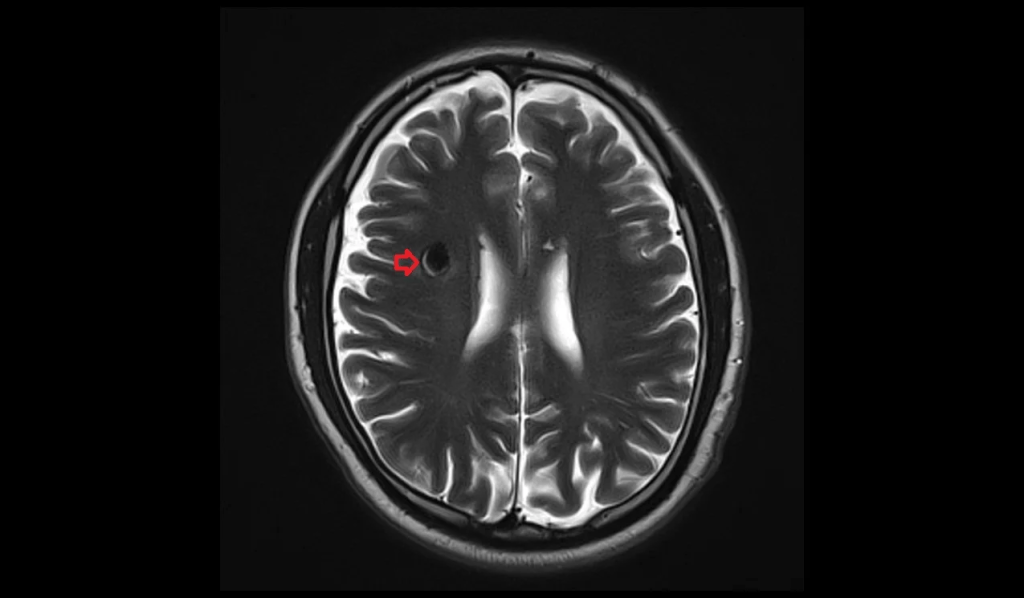

MRI—Gold standard

– “Popcorn” or “mulberry” appearance with a mixed-signal core (due to blood at different stages).

– Surrounded by a hypointense hemosiderin rim (from previous microbleeds).

Best seen on:

– T2-weighted images

– Gradient Echo (GRE) or SWI for blooming artifact from hemosiderin.

T2 axial images show cavernoma